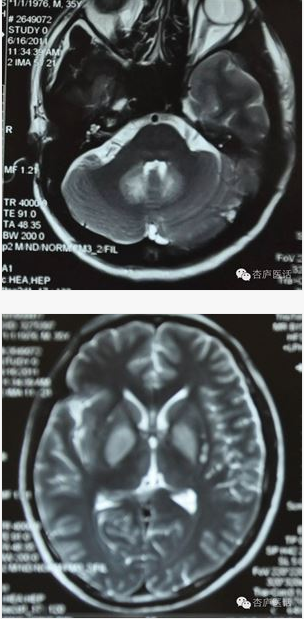

▲ 患者郭某中毒后头颅MRI表现提示基底节区对称性异常信号

山豆根中毒在临床中并不少见。大多数都是在服用中药山豆根后出现头晕和行走不稳症状,头颅磁共振多见小脑齿状核对称性病变。这种轻微的病变在应用激素治疗后往往恢复较好,症状可以完全缓解。但严重的山豆根中毒可以造成脑干、小脑、基底节区及大脑皮层的对称性病变,这种病变往往会症状较重,恢复效果很差。